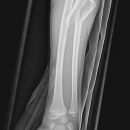

Galeazzi-Fraktur